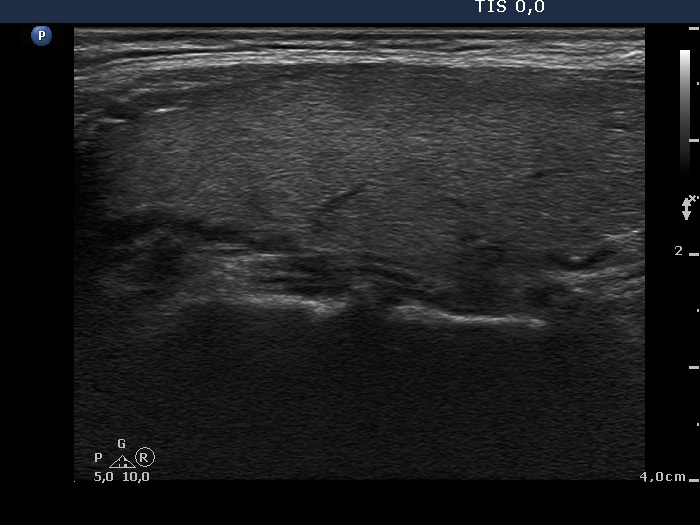

Case 850 (ultrasonographic picture 2)

Upper part of the right lobe, longitudinal view.